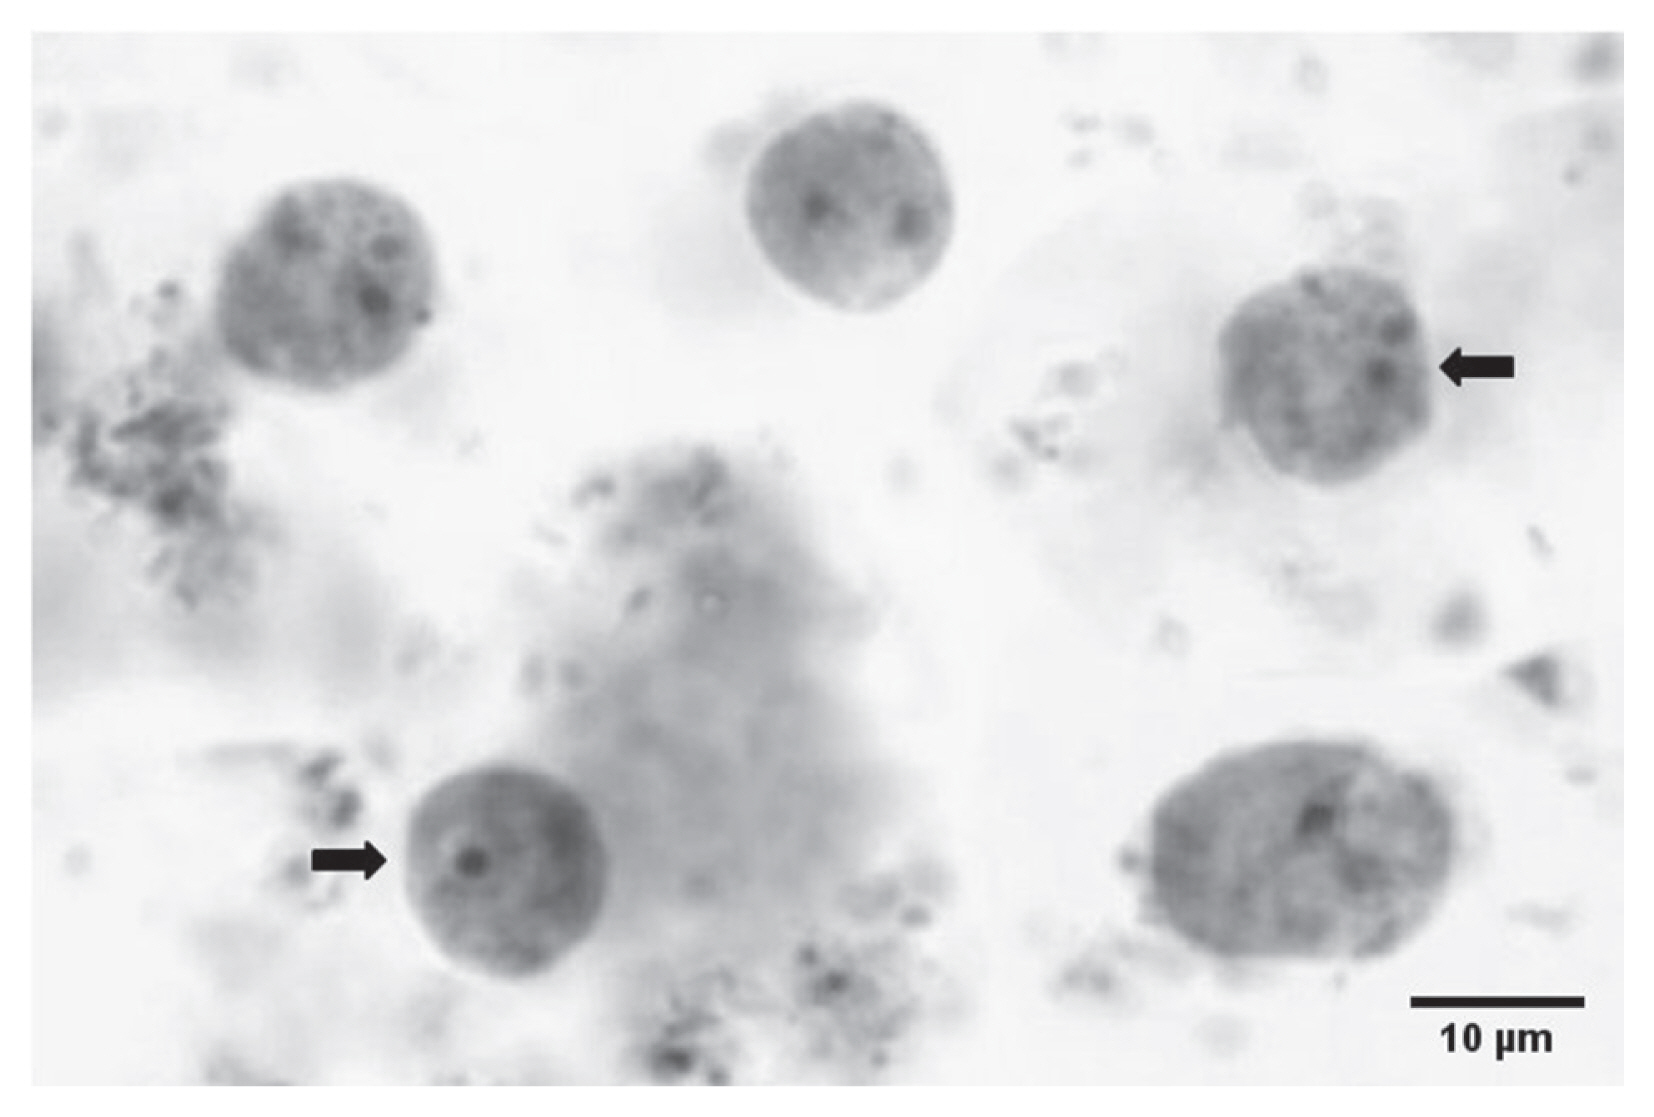

Stool samples (1 per patient) were obtained from all participants on the day of the interview or shortly afterwards. Fresh feces (within half an hour of collection) were microscopically screened for intestinal protozoa and instantly fixed; 1 part in 10% formalin and 1 part in 70% ethanol. Properly labeled preserved specimens were transported to the Medical Laboratory at Taif University’s College of Applied Medical Sciences. Smear preparations from formalin-fixed specimens were permanently stained inside the laboratory with iron-haematoxylin, Ziehl-Neelsen and trichrome stain, as mentioned elsewhere [14,15]. The ethanol-fixed specimens were kept at −20°C for Dientamoeba DNA detecting PCR.